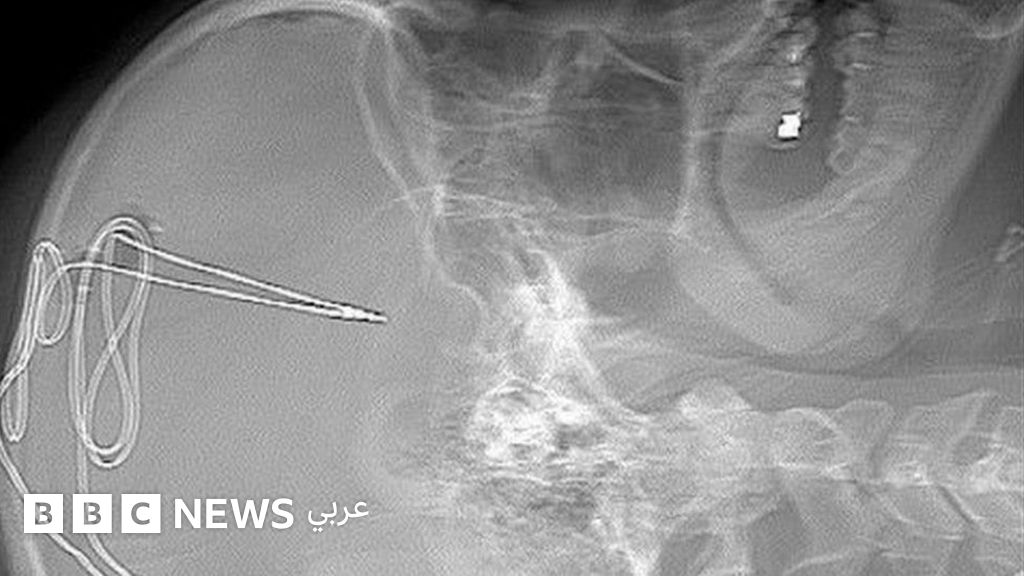

ويبدأ الإعداد لهذه الجراحة بسلسلة من فحوصات مسح الدماغ، بعدها يبدأ الجراحون في ثقب الجمجمة لإدخال أنبوب كهربائي متناهي الصغر لا يتجاوز حجمه ملليمتر في منطقة محددة من المخ وتساعد المريض على التحكم في الدوافع مثل الإدمان والتحكم في الذات.

كما تُزرع بطارية تحت عظام الترقوة ثم يخضع نشاط المخ للمراقبة عن بعد على يد فريق من الأطباء البشريين، والنفسيين، وخبراء الإدمان لتحديد إذا ما كانت الرغبة في تناول المخدر تتراجع أم لا.